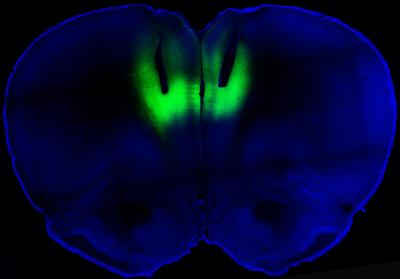

"When we turn on a laser light in the prelimbic region of the prefrontal cortex, the compulsive cocaine seeking is gone," says Antonello Bonci, MD, scientific director of the intramural research program at the NIH's National Institute on Drug Abuse (NIDA), where the work was done. Bonci is also an adjunct professor of neurology at UCSF and an adjunct professor at Johns Hopkins University (Baltimore, MD).

Electrophysiological studies involving these rats have shown that they have extremely low activity in the prefrontal cortex—a brain region fundamental for impulse control, decision making, and behavioral flexibility. Similar studies that imaged the brains of humans have shown the same pattern of low activity in this region in people who are compulsively addicted to cocaine.

To test whether altering the activity in this brain region could impact addiction, Chen and his colleagues employed optogenetics to shut the activity on and off using a laser. First, they took light-sensitive proteins called rhodopsins and used genetic engineering to insert them into neurons in the rat's prefrontal cortex. Activating this region with a laser tuned to the rhodopsins turned the nerve cells on and off. Turning on these cells wiped out the compulsive behavior, while switching them off turned the non-addicted ones into addicted, the researchers found.